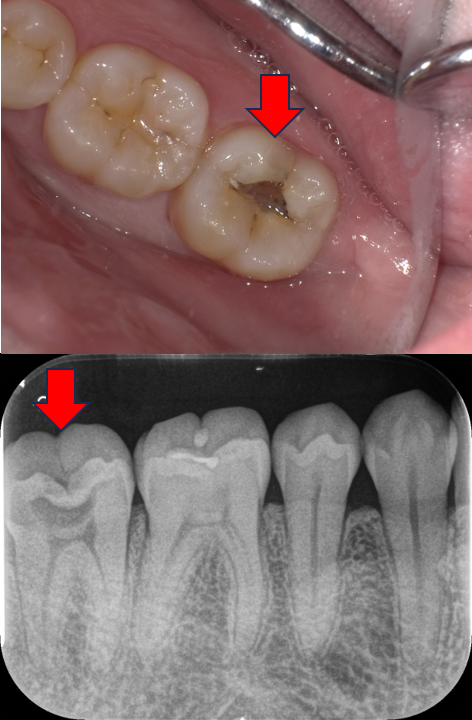

「神経を抜く」と言われた歯を残した症例|つくば市のセカンドオピニオン・セレック治療(30代女性)

Before

After

| 主訴 | 虫歯治療の相談。他院で「神経を抜く」と言われたが、可能であれば神経を残して治療したい。 |

| 診断名 | 深い虫歯(象牙質う蝕・C2) |

| 治療方法 | セレックシステムによる精密セラミック修復(神経の保護を含む) |